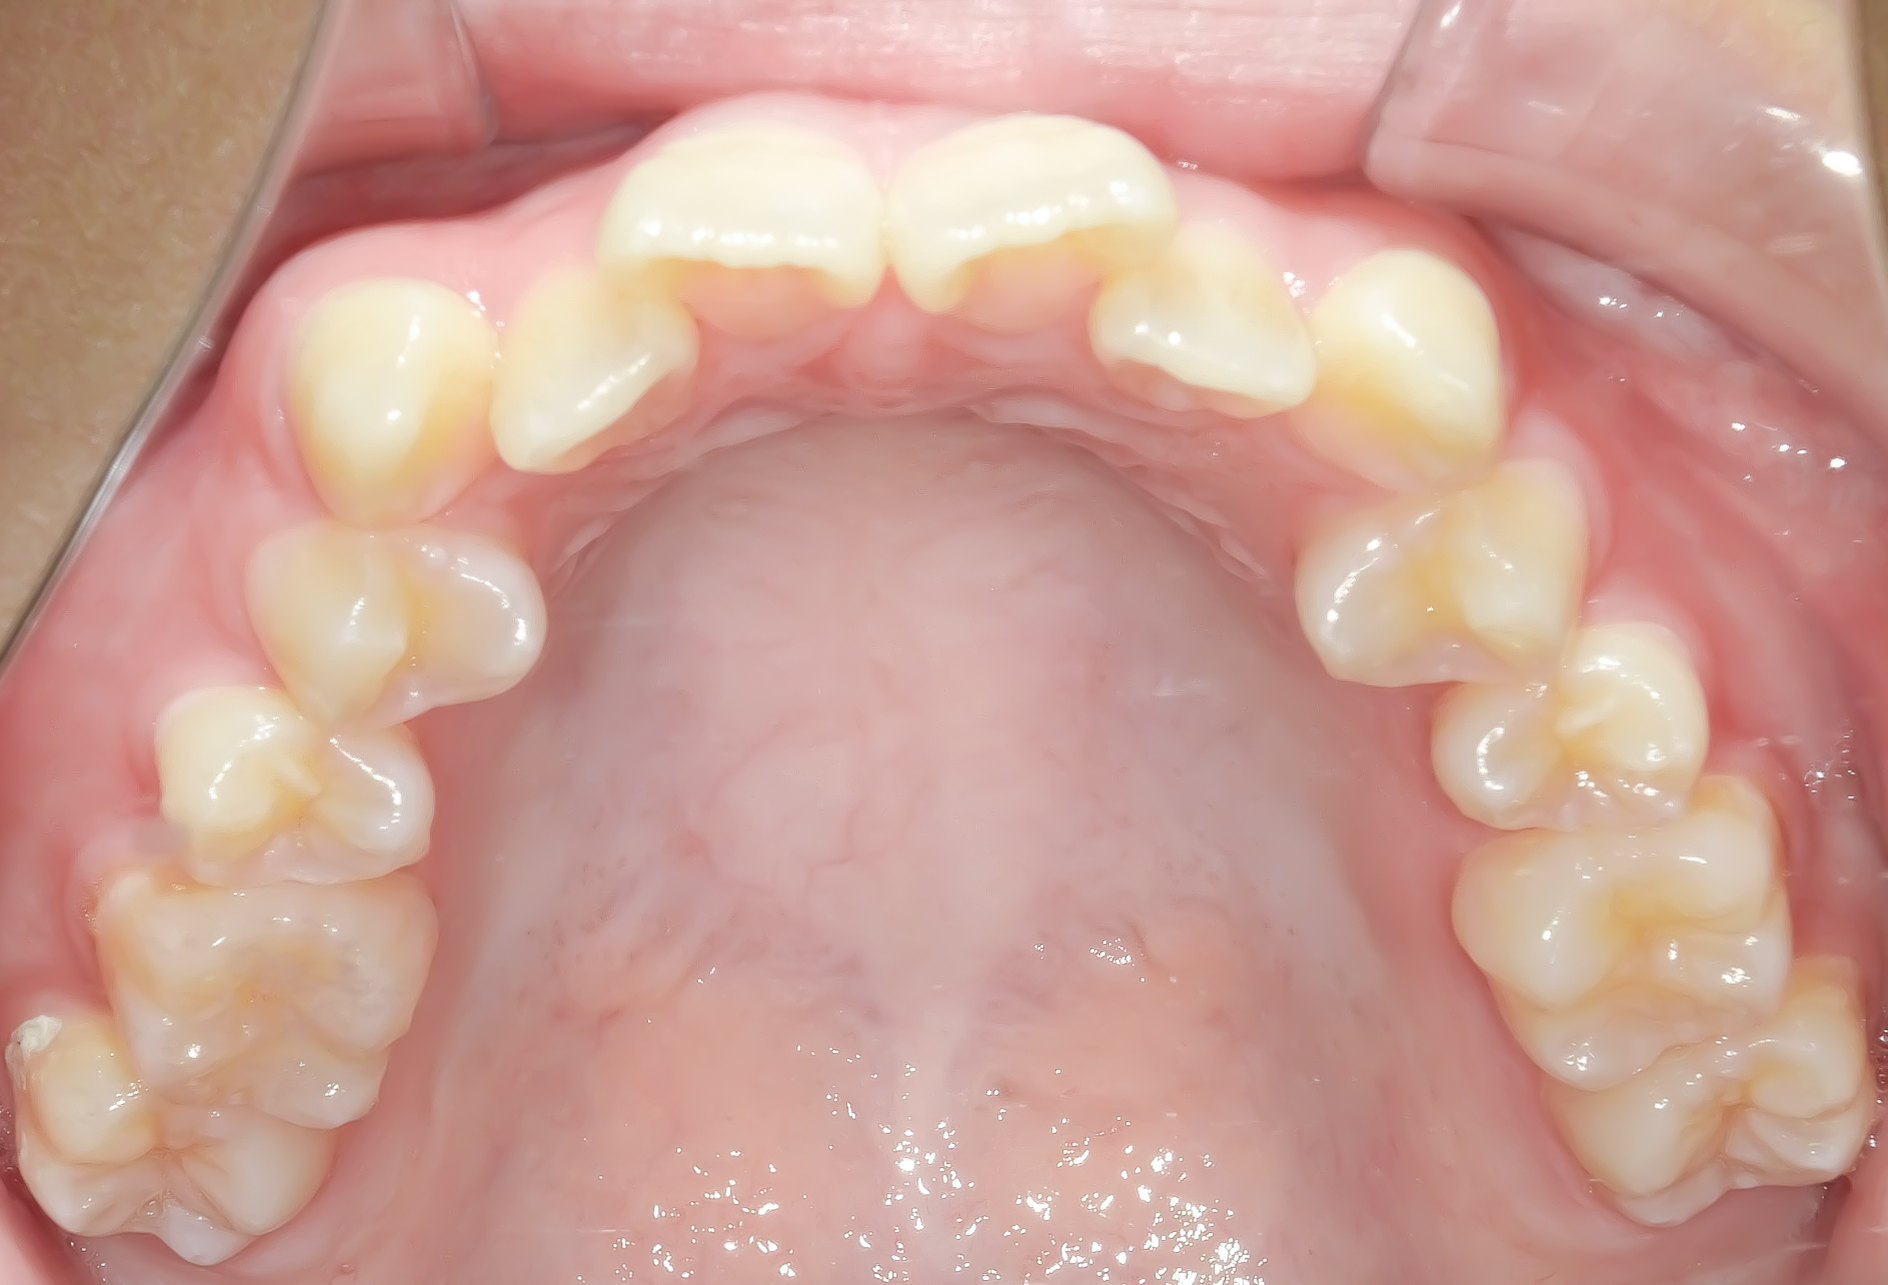

Before

上顎の前歯部あたりに重度のガタガタ(叢生)を認めます。

下顎には軽度の叢生を認めます。